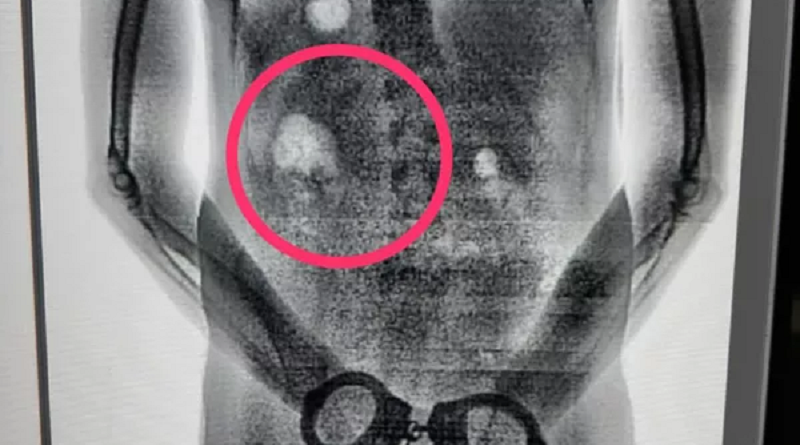

Detentos são flagrados tentando entrar em presídio com tabletes de maconha no estômago no Pará. — Foto: Reprodução / Seap

Presos tiveram o corpo escaneado após retorno da saída temporária para o Círio de Nazaré, segundo a Secretaria de Administração Penitenciária.

De acordo com a Secretaria de Administração Penitenciária (Seap), a revista ocorreu na terça (27), quando os presos retornavam da saída temporária do Círio. Os dois foram submetidos aos procedimentos de segurança incluindo a revista no escaneamento do corpo inteiro, que detecta objetos ingeridos, sem remover a roupa ou contato físico.